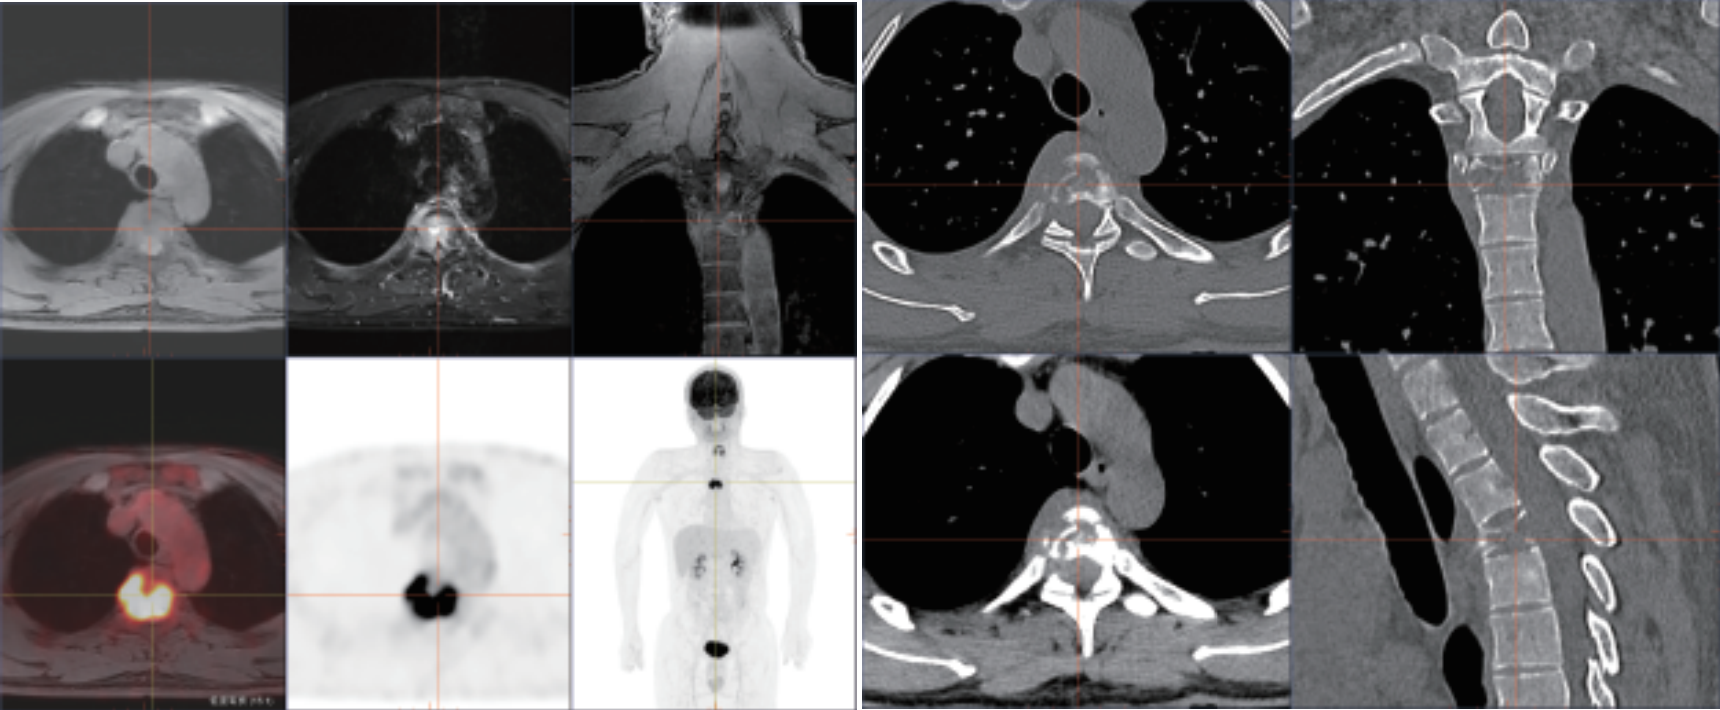

? 強(qiáng)大的查體功能:PET和MRI同步掃描,MR 圖像可實(shí)現(xiàn)任意角度的重建和融合, 多角度的觀察解剖和代謝信息,多維度與 PET 實(shí)現(xiàn)軸、冠、矢三維圖像精確融合, 一次檢查便可篩查全身危險(xiǎn)病灶,帶來更好的科研體驗(yàn)。

? 小病灶高精度成像:TOF飛行時(shí)間技術(shù)精確定位真符合時(shí)間發(fā)生位置,顯著提升圖像對(duì)比度和信噪比,提供更為優(yōu)質(zhì)的臨床圖像,結(jié)合3D光梭成像,可精準(zhǔn)檢測(cè)組織微小病變,為診斷提供更為多元和準(zhǔn)確依據(jù)。

相關(guān)病例成像圖